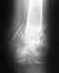

Операция тут, конечно, не по жизненным показаниям. но без нее большие шансы, что вилка голеностопного сустава будет нестабильна, то есть будут постоянные боли при ходьбе. Методик операций несколько, смысл в том, чтобы тем или иным устройством сблизить и удержать берцовые кости до рубцевания синдесмоза. При застарелом повреждении, т.е. при отсрочке операции более 2-3 недель, этого уже может быть недостаточно, может потребоваться пластика синдесмоза каким-либо материалом.